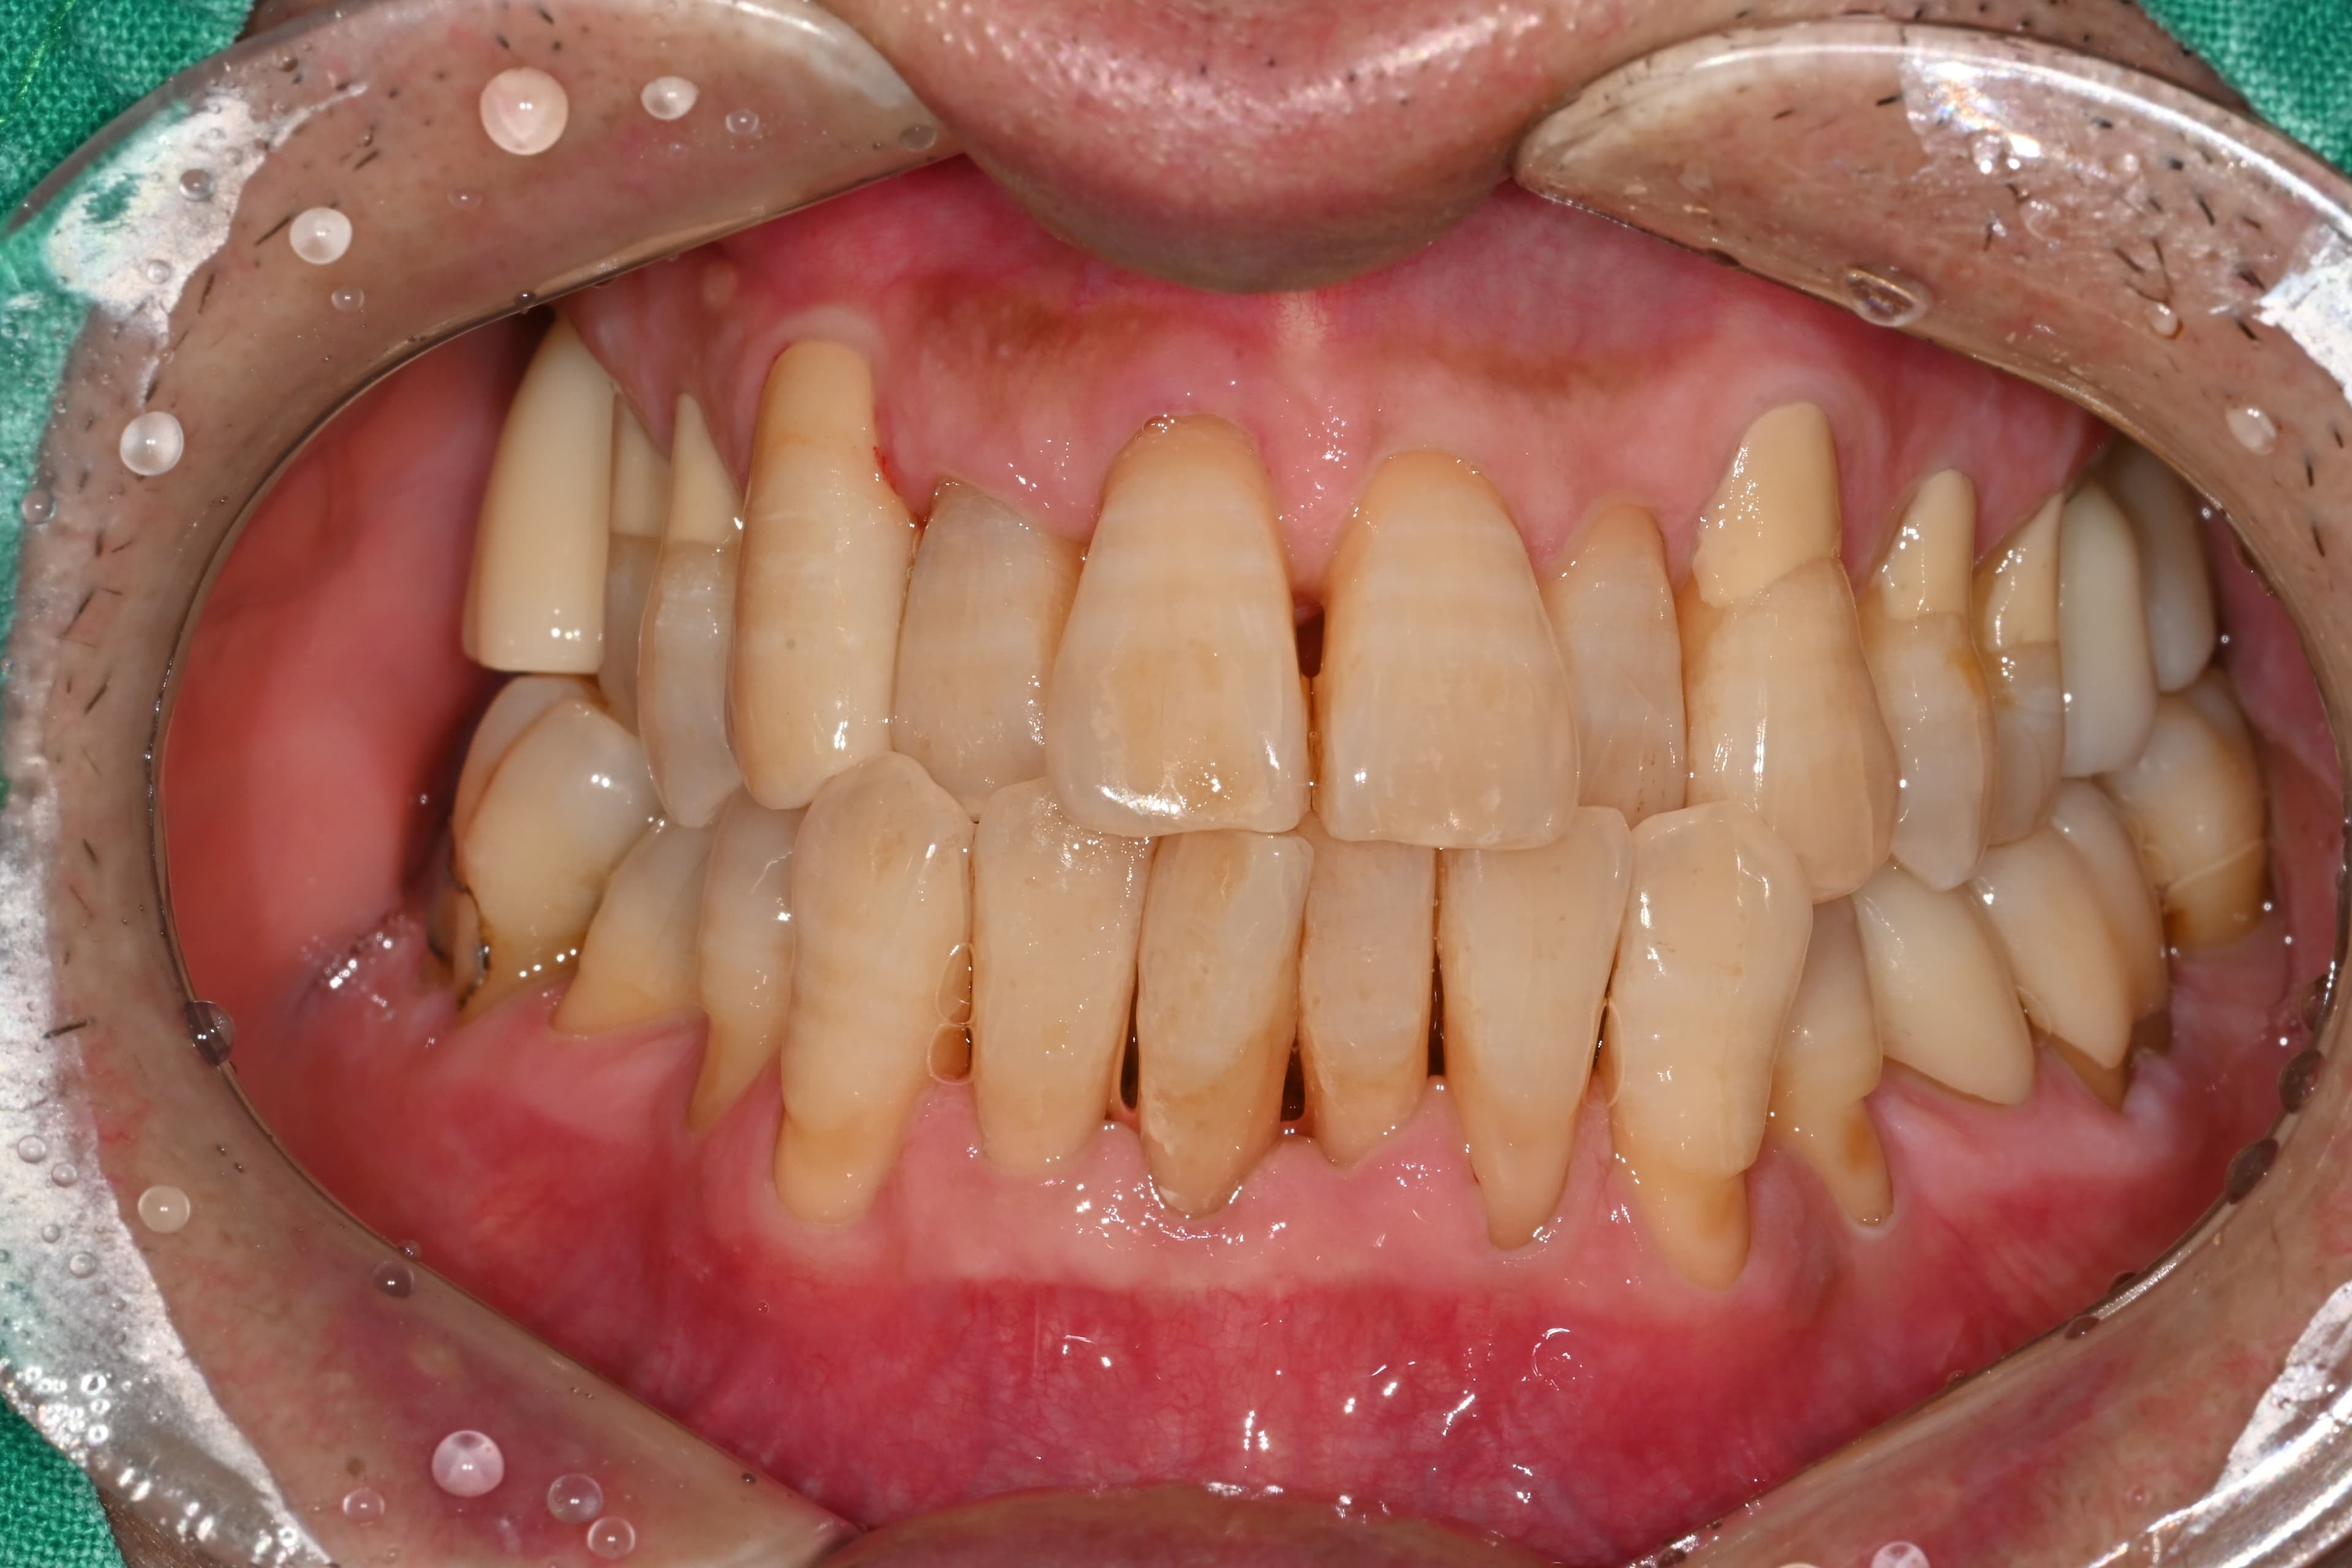

"多亏定期管理

50多岁所有牙齿都很健康"

Before

After

牙结石和牙龈炎症严重的状态

通过定期洗牙和管理保持健康